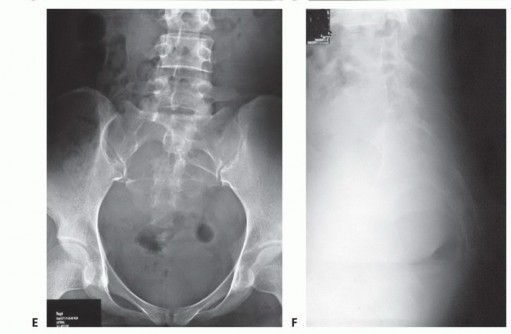

التصوير بالأشعة السينية العادية

قد تكون صور الأشعة السينية العادية غير واضحة في المراحل المبكرة من المرض. ومع ذلك، يمكن أن تساعد في تشخيص بعض الأورام، مثل الورم الحبلي الذي غالبًا ما يقع في الجزء السفلي من العجز، أو الأورام الكبيرة والمحللة تمامًا مثل ورم الخلايا العملاقة أو الكيس العظمي المتمدد في الجزء العلوي من العجز. تُعد الأشعة السينية ضرورية لإعطاء نظرة عامة ومتابعة ما بعد الجراحة.

التصوير المقطعي المحوسب والرنين المغناطيسي

- التصوير المقطعي المحوسب (CT): يُعد بتقنية التباين الوريدي الأسلوب الأمثل لتقييم مدى انتشار الورم في العظم وتدميره، والتكلسات المحتملة، والموقع التشريحي، والإمداد الدموي، وعلاقة الورم بالأعضاء الحشوية. يساعد في التفريق بين الأورام الحميدة والخبيثة.

- التصوير بالرنين المغناطيسي (MRI): بتقنية التباين، يُعد حاسمًا لتصوير الأنسجة الرخوة ومدى انتشار الورم فيها، وعلاقته بالأنسجة المحيطة (مثل الأوعية الدموية والأعصاب والعضلات والأعضاء الحشوية). يُعتبر الأسلوب الأمثل لتصوير الأنسجة الرخوة نظرًا لقدرته الفائقة على التمييز مقارنةً بالتصوير المقطعي.